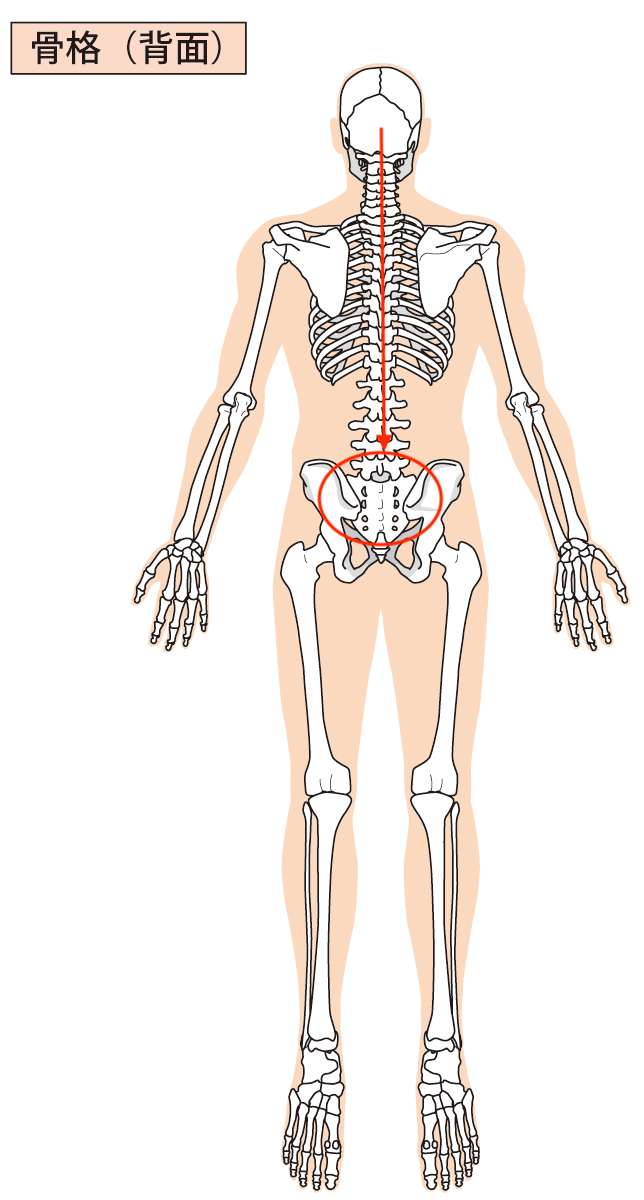

骨盤の歪みと頭痛の関係は、簡単に説明すると、背骨を通して骨盤と頭がつながっているということです。

どういうことかというと、こちらの画像をご覧ください。

赤丸の真ん中にあるのが「仙骨」という骨です。

その「仙骨」という骨の上に背骨が乗っています。

その「背骨」を上まで上がっていくと、一番上で背骨の上に頭が乗っています。

つまり、骨が連なってすべてつながっているということです。

だから、骨盤が少し歪むだけで、その歪みが背骨に伝わり、頭にまで伝わっていくということです。